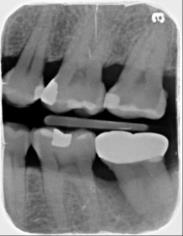

A圖為#37根管治療完後的三個月放射線攝影根尖片。

術後一年之全口X光片, #37近心側可見明顯骨充填與放射線密度增加。 牙周再生手術完成一年後追蹤,全口牙齦發炎狀況改善,牙周組織呈現健康狀況。#37金屬燒附陶瓷牙冠製作完成。